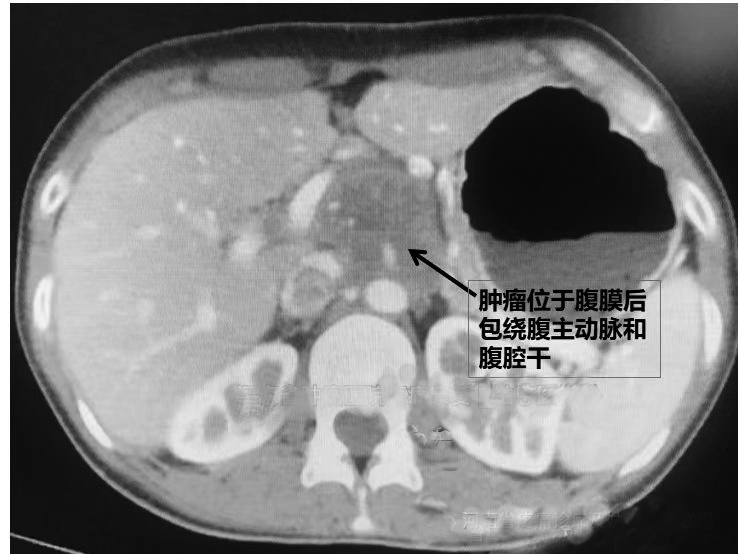

河南省肿瘤医院疼痛康复与姑息医学科主任谢广伦接诊了韩先生。仔细了解韩先生的病史,看过CT影像片后,谢广伦建议进行“CT引导下腹腔神经丛毁损联合肿瘤内毁损药物注射”,在控制疼痛的同时,对肿瘤进行毁损药物注射,可减小肿瘤并延缓肿瘤转移,有止痛和减瘤的双重作用。这种技术只用几根穿刺针就可以达到治疗的目的,创伤非常小。

CT引导下腹腔神经毁损是治疗癌性腹痛的方法之一。这种技术仅用两根直径0.5毫米的穿刺针,精确地将针尖穿刺到导致腹痛的责任神经丛——腹腔神经丛周围,然后注入药物破坏神经传导,从而消除疼痛。但是,在常规的腹腔神经丛毁损过程中,没有对肿瘤进行治疗,甚至肿瘤一直在生长,导致止痛有效率低(仅为70%左右),或者虽然有效但是很快又出现疼痛。针对这种情况,谢广伦团队通过深入研究,开展了“腹腔神经丛毁损联合肿瘤内毁损药物注射”技术,在进行神经毁损的同时把毁损药物注射到肿瘤内部。在止痛效果更好(有效率可提高到90%左右)的同时,肿瘤也在药物的作用下缩小、坏死或失活,因此病人的生活质量更好,存活时间更长。